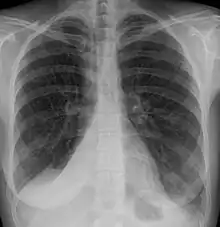

Atelectasis is the partial collapse or closure of a lung resulting in reduced or absent gas exchange. It is usually unilateral, affecting part or all of one lung.[2] It is a condition where the alveoli are deflated down to little or no volume, as distinct from pulmonary consolidation, in which they are filled with liquid. It is often referred to informally as a collapsed lung, although more accurately it usually involves only a partial collapse, and that ambiguous term is also informally used for a fully collapsed lung caused by a pneumothorax.[1]

It is a very common finding in chest X-rays and other radiological studies, and may be caused by normal exhalation or by various medical conditions. Although frequently described as a collapse of lung tissue, atelectasis is not synonymous with a pneumothorax, which is a more specific condition that can cause atelectasis. Acute atelectasis may occur as a post-operative complication or as a result of surfactant deficiency. In premature babies, this leads to infant respiratory distress syndrome.

Clinically significant atelectasis is generally visible on chest X-ray; findings can include lung opacification and/or loss of lung volume. Post-surgical atelectasis will be bibasal in pattern. Chest CT or bronchoscopy may be necessary if the cause of atelectasis is not clinically apparent. Direct signs of atelectasis include displacement of interlobar fissures and mobile structures within the thorax, overinflation of the unaffected ipsilateral lobe or contralateral lung, and opacification of the collapsed lobe. In addition to clinically significant findings on chest X-rays, patients may present with indirect signs and symptoms such as elevation of the diaphragm, shifting of the trachea, heart and mediastinum; displacement of the hilus and shifting granulomas.[10]